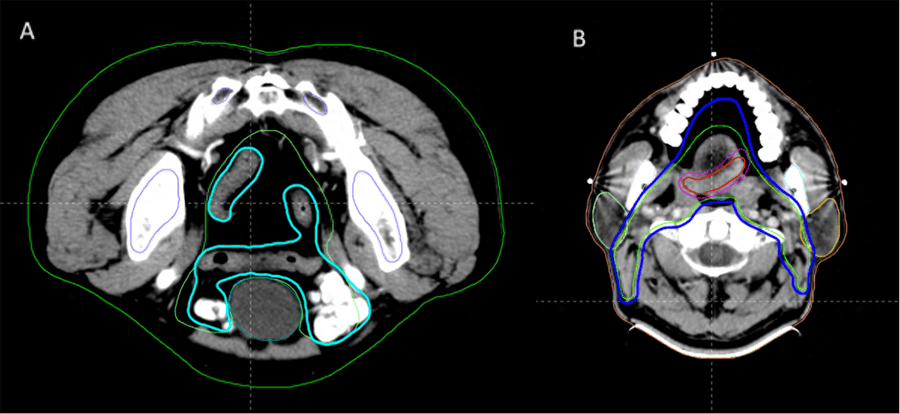

肿瘤中心在2022年11月和2023年6月分别引进了两套国内先进的人工智能辅助靶区勾画系统,新型的智能勾画系统相比于传统的基于图谱(Atlas-based)的自动勾画更具有优势,成功实现了复杂靶区的自动勾画,以鼻咽癌靶区勾画为例,传统手工勾画需要2-3小时,而自动勾画只需2分钟,大大简化了放射治疗的流程,缩短了患者从定位到治疗的等待时间,减少了患者的住院周期,对进一步合理配置医疗资源具有重要意义。

盆腔和头颈部靶区自动勾画效果